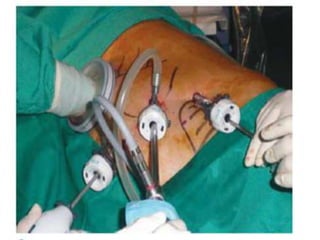

LAPAROSCOPIC SPLENECTOMY

Position- right side down

 Ports-

1. At midline and 4 cm below the spleen tip,

2. Near the tip of the 11th rib along the posterior axillary line

3. Half way between the other two, along the anterior axillary

line. Occasionally, a fourth port may be required.